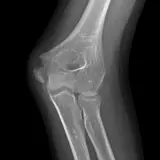

MSK Radiographs